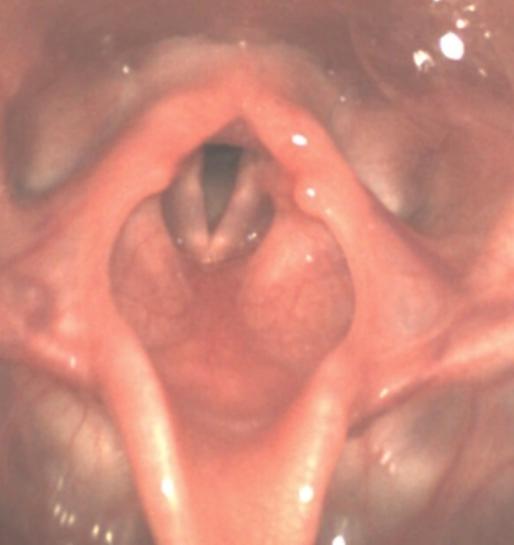

Blick mit dem Endoskop von oben auf den Kehlkopf eines Kleinkindes. Es handelt sich um einen Normalbefund.